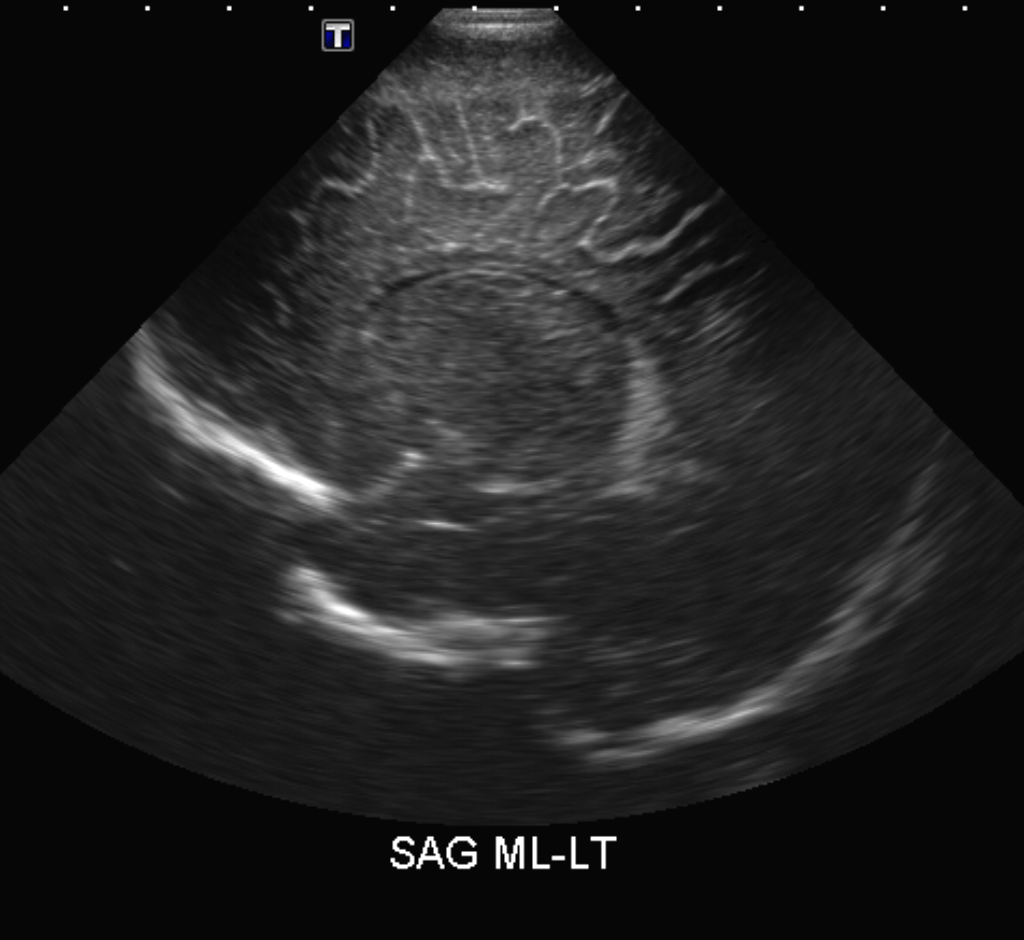

Info Images Findings Impression Reco/Acuity Case Images View Images / Launch Visage Case Notes History Full term infant. We are asked to evaluate posterior fossa cyst. Exam Gray scale and Doppler Ultrasonographic examination of the head. Prior Study N/A Dicom View Reference Material

Section 1 Submit Findings Case149 Findings Brain The brain is immature. Yes No There is under-sulcation and open sylvian fissures. Yes No There is/are multiple hypoechoic areas in the periventricular white matter. Yes No There is/are multiple hyperechoic areas in the periventricular white matter. Yes No There is diffuse cerebral edema with diffusely increased echogenicity of the brain parenchyma and loss of grey white matter differentiation. Yes No The thalami/basal ganglia are hypoechoic. Yes No There is periventricular calcification. Yes No There is intra-parenchymal calcification. Yes No CSF spaces/ventricular system There is a prominence of the extra axial fluid spaces. Yes No There are debris/septations in the extra axial fluid spaces. Yes No There are debris/septations in the ventricles. Yes No There is a subdural collection on the right/left side. Yes No There is prominence of the ventricular system. Yes No There is an asymmetry of the ventricular system. Yes No There is a cavum septum pellucidum. Yes No There is a midline shift towards right/left. Yes No The choroid plexus is bulky/lobulated. Yes No There is a choroid plexus cyst measuring… Yes No There are debris/clots in the occipital horn. Yes No There is a posterior fossa cyst measuring… Yes No The tentorium is elevated/depressed. Yes No The lateral ventricle/s are dilated. Yes No The third ventricle is dilated. Yes No The 4th ventricle is dilated. Yes No There are pseudo cysts. Yes No Germinal matrix hemorrhage (Only in the premature infants): Please do not answer if the patient is a full term. There is a germinal matrix hemorrhage, consistent with a grade I hemorrhage. Yes No There is an intraventricular extension consistent with a grade II hemorrhage. Yes No There is an intraventricular extension with the dilatation of ventricles, consistent with a grade III hemorrhage. Yes No There is an intra-parenchymal extension, consistent with grade IV hemorrhage. Yes No On color Doppler examination, the Resistive index in the anterior cerebral artery is… There is a loss of the diastolic flow on the Doppler exam. Yes No There is altered vascularity on Doppler imaging. Yes No There is an AVM in the region of… Yes No